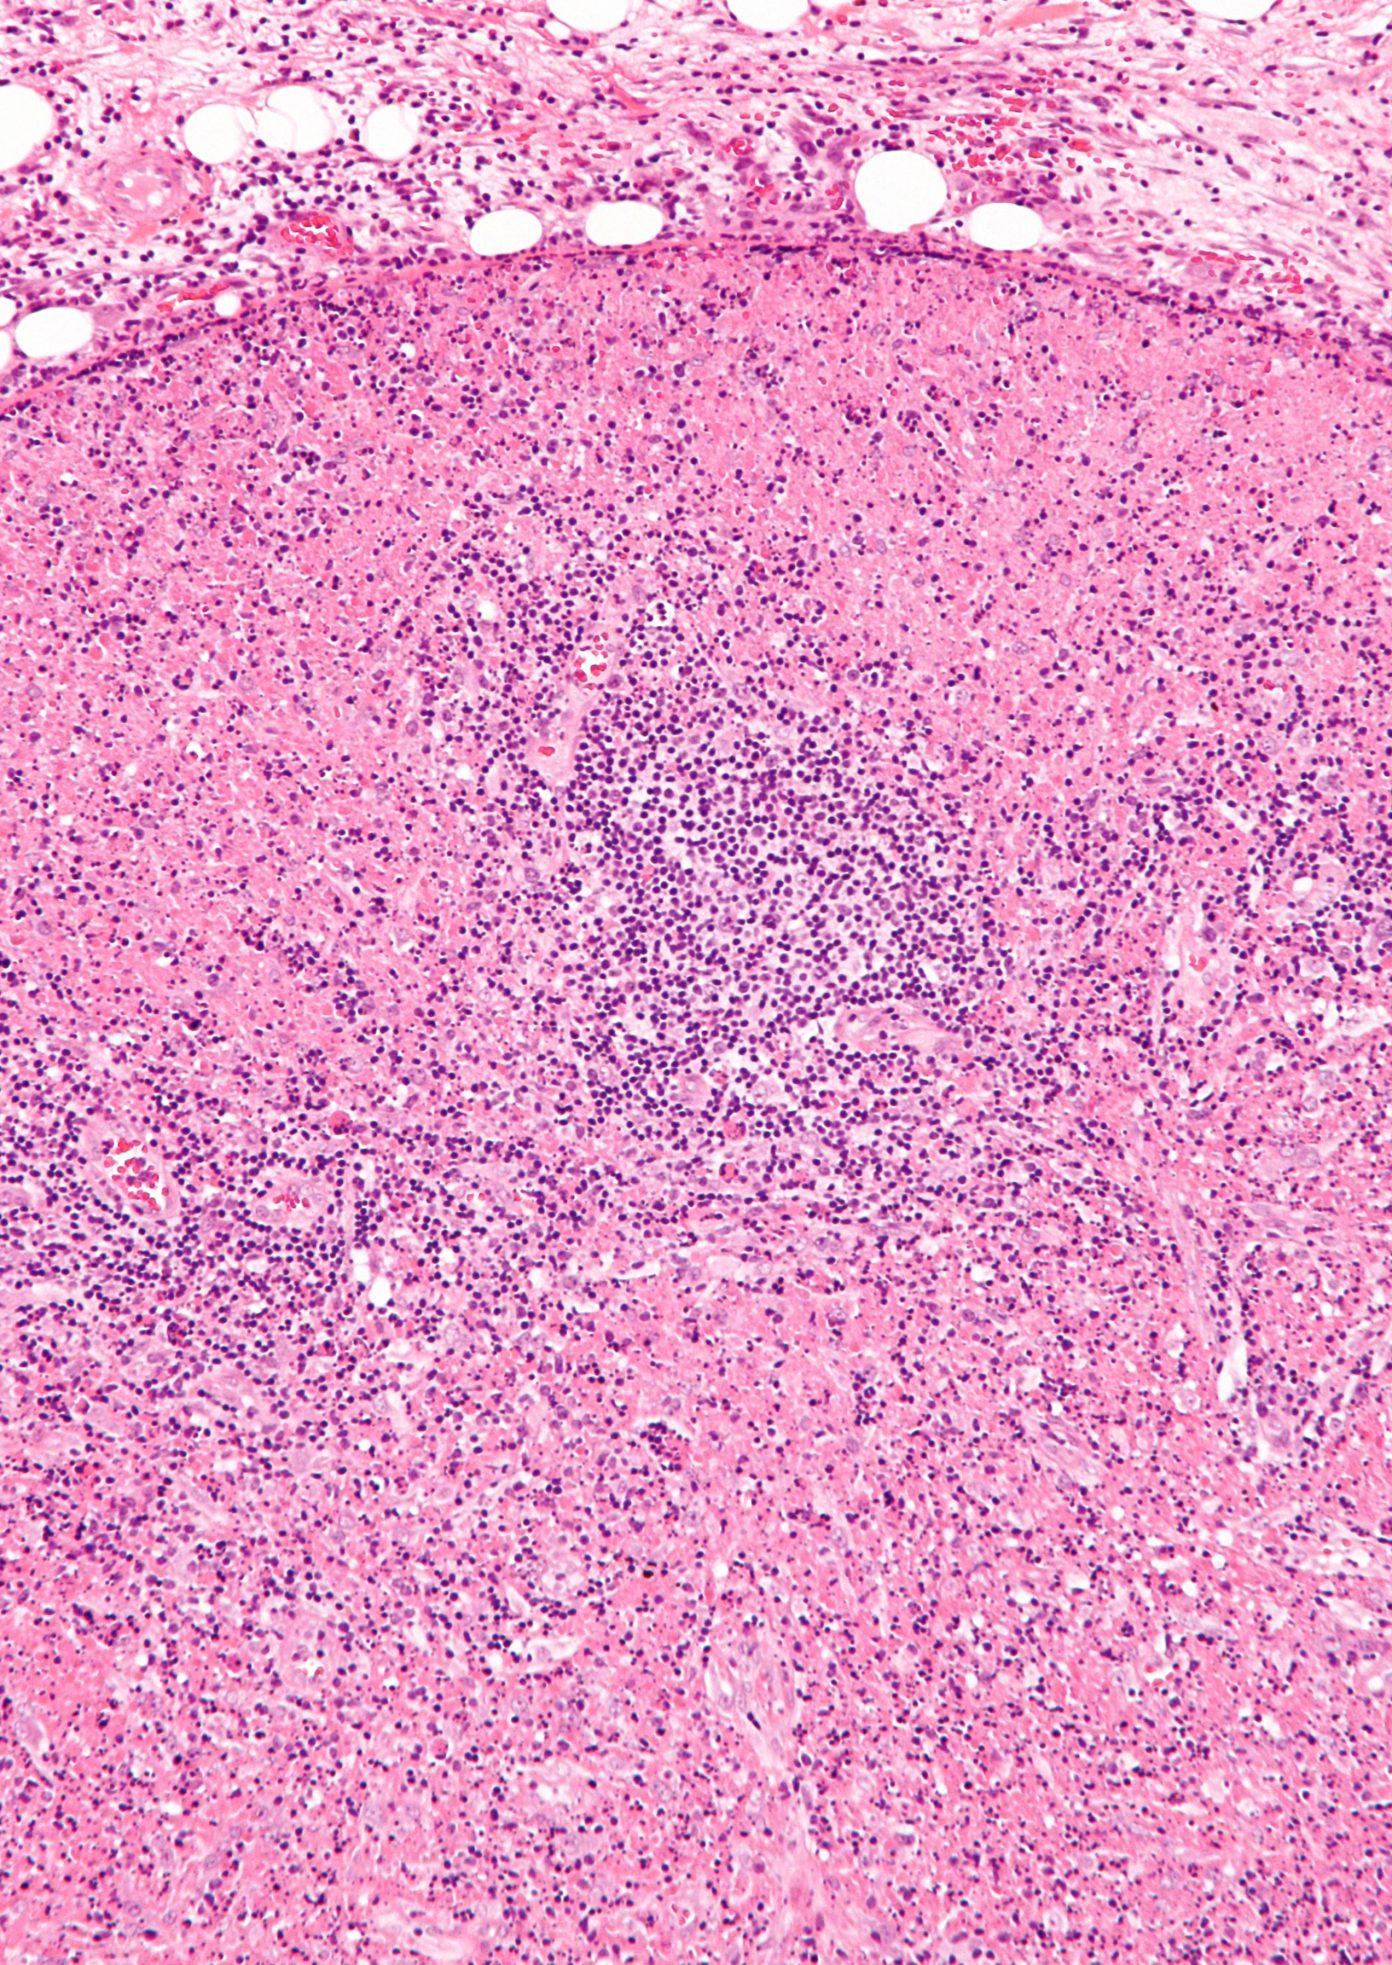

As the symptoms are non-specific, differential diagnoses, including viral infections, . The basis of its diagnosis relies on the histological examination of lymph nodes, which typically reveals necrosis surrounded . Since the first description of the disease by the Japanese pathologists Kikuchi and Fujimoto, 20,39 its etiology has remained unknown, although environmental factors, in particular viruses, have been suspected. Elle touche généralement les jeunes adultes ( 40 ans), mais peut toucher toute tranche d’âge. It may be triggered by an infection or .Schlagwörter:Kikuchi-Fujimoto Disease SymptomsJapanese Disease Kikuchi Les signes et symptômes de la maladie de Kikuchi-Fujimoto sont la fièvre, l’hypertrophie des ganglions lymphatiques (lymphadénopathie), les éruptions cutanées et les maux de tête [5]. We report two cases of Kikuchi-Fujimoto disease.The disease is characterised by a unilateral posterior cervical lymphadenopathy.Kikuchi disease, also called histiocytic necrotizing lymphadenitis or Kikuchi-Fujimoto disease, is an uncommon, idiopathic, generally self-limited cause of lymphadenitis. Prompt diagnosis with excisional lymph node biopsy is imperative to diagnose and manage patients appropriately. in 1972 in Japan.Kikuchi-Fujimoto disease, also known as subacute necrotizing lymphadenitis or subacute necrotizing histiocytosis, is an idiopathic disease . Lactate dehydrogenase and alanine aminotransferase concentrations can be raised; neutropenia and lymphopenia are common. Less frequent symptoms include weight loss, nausea, vomiting, sore throat. It has been associated with autoimmune disorders, of which systemic lupus erythematosus is the most outstanding.Kikuchi disease, also called histiocytic necrotizing lymphadenitis or Kikuchi-Fujimoto disease, is an uncommon, idiopathic, generally self-limited cause of . Weight loss, skin rash, . Syn: Histiozytäre nekrotisierende Lymphadenitits Engl: Kikuchi disease, histiocytic necrotizing lymphadenitis Histr: Erstbeschreibung im Jahre 1972 in Japan durch Kikuchi und Fujimoto Vork: meist junge Frauen Def: sehr unscharf definierte, selbstlimitierte febrile zervikale Lymphadenitis unklarer Genese; diskutiert wird .Kikuchi-Fujimoto disease (KFD) is a benign and self-limited disorder, characterized by regional cervical lymphadenopathy with tenderness, usually accompanied with mild fever and night sweats. [QxMD MEDLINE Link]. It is generally believed that the pathogenesis of this disease included two aspects: viral infection and autoimmune response . Patients present with localized .Kikuchi-Fujimotos disease (KFD, Kikuchi-Fujimoto-Krankheit) ist eine vorwiegend zervikale (am Hals auftretende) fiebrige Lymphadenopathie (Lymphknotenvergrößerung) ungeklärter Genese, die sich histologisch als histiocytische nekrotisierende Lymphadenitis darstellt.deTularämie-Lymphadenitis | Die Pathologie – Springerlink. Histiocytic necrotising lymphadenitis is also known as Kikuchi disease, Kikuchi–Fujimoto disease, and histiocytic necrotising .Kikuchi disease is a rare, benign condition of unknown cause that causes fever and cervical lymphadenopathy.Schlagwörter:Kikuchi-Fujimoto DiseaseKikuchi Disease

Kikuchi-Fujimoto disease (KFD), or histiocytic necrotizing lymphadenitis, was first described in 1972 simultaneously by Kikuchi1 and Fujimoto and colleagues2 as a lymphadenitis with focal proliferation of histiocytic cells and abundant karyorrhectic debris.Schlagwörter:Kikuchi-Fujimoto DiseaseAnamarija M Perry, Sarah M Choi It can be confused with lymphoma, adenocarcinoma metastasis and tuberculosis. Neurological complications of Kikuchi-Fujimoto disease were occasionally reported although the specific . Kikuchi-Fujimoto disease is an extremely rare disease known to .This review points out the etiology of KFD with cervical lymphadenopathy alongside its clinical presentation, histological highlights, lab investigations, . Kikuchi-Fujimoto disease (also known as Kikuchi disease or histiocytic necrotizing lymphadenitis), is a disease characterized by .Kikuchi-Fujimoto-Lymphadenitis bei 29-jähriger Patientinspringermedizin.